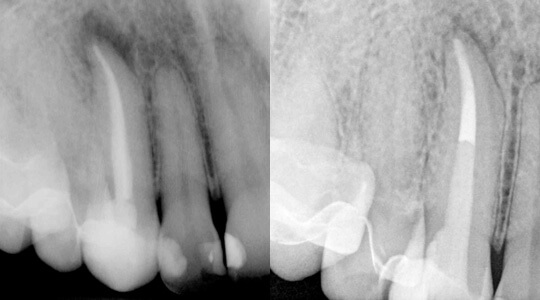

Haben sich an einem Zahn Bakterien im Sinne einer Karies angesiedelt, so besteht die Möglichkeit, dass der Zahnnerv infiziert wird (Bild Mitte). Als Folge dessen reagiert der Zahnnerv mit einer Entzündung, die zu einem Absterben des Nervens führen kann. Die Bakterien können sich dann im Wurzelkanalsystem innerhalb des abgestorbenen Nervgewebes vermehren und im Kieferknochen eine Entzündung hervorrufen. Diese Entzündung kann zu einer häufig zu beobachtenden Aufklopfempfindlichkeit des erkrankten Zahnes und einem Anschwellen der betroffenen Region führen. In seltenen Fällen können aber auch Unfälle oder zahnärztliche Behandlungen Ursache für die Erkrankung eines Zahnnervs sein.

Ziel dieser Maßnahmen ist es, das ursprüngliche Kanalsystem möglichst in einen keimarmen und sauberen Zustand zu bringen. Dieses hört sich zunächst sehr einfach an, doch bergen z. B. kleine Seitenkanäle die Gefahr einer möglichen Reinfektion (siehe Pfeile in Bild links und rechts). Auch diese müssen sorgfältig gereinigt und möglichst perfekt aufgefüllt werden. Aus diesem Grund nehmen wir uns für Ihren Zahn die entsprechende Zeit, um die oben beschriebene chemomechanische Desinfektion durchzuführen.

Manchmal weisen die Zähne auch komplizierte anatomische Merkmale auf, die wir mit besonderer Sorgfalt behandeln müssen. Dazu gehören zum Beispiel eine überdurchschnittliche Anzahl an Wurzelkanälen (Bild links) oder starke Wurzelkrümmungen (Bild rechts): Oberer Backenzahn mit trotz starker Wurzelkrümmung erfolgreich gereinigten und aufgefülltem Wurzelkanalsystem.